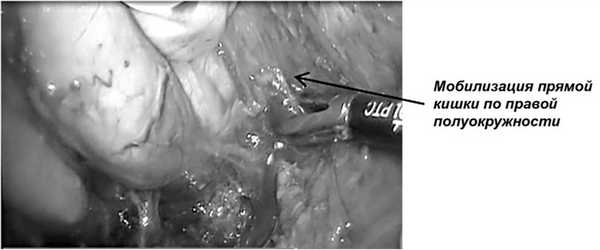

На этом этапе мануально-ассистированная техника имеет преимущества, особенно у тучных пациентов, при узком тазе и значительных размерах опухоли, помогает понять истинные размеры опухоли, ее протяженность, подвижность, возможность выполнения сфинктерсохраняющей операции. При опухолях малых и умеренных размеров веерообразный ретрактор и рука хирурга поочередно создают «каньон» для лапароскопа с 30-градусной оптикой и инструмента для бескровной диссекции тканей в плоскости собственной фасции мезоректума со всех сторон (рис. 8).

Рис. 8. Выделение правой полуокружности мезоректума с использованием мануально-ассистированной техники.